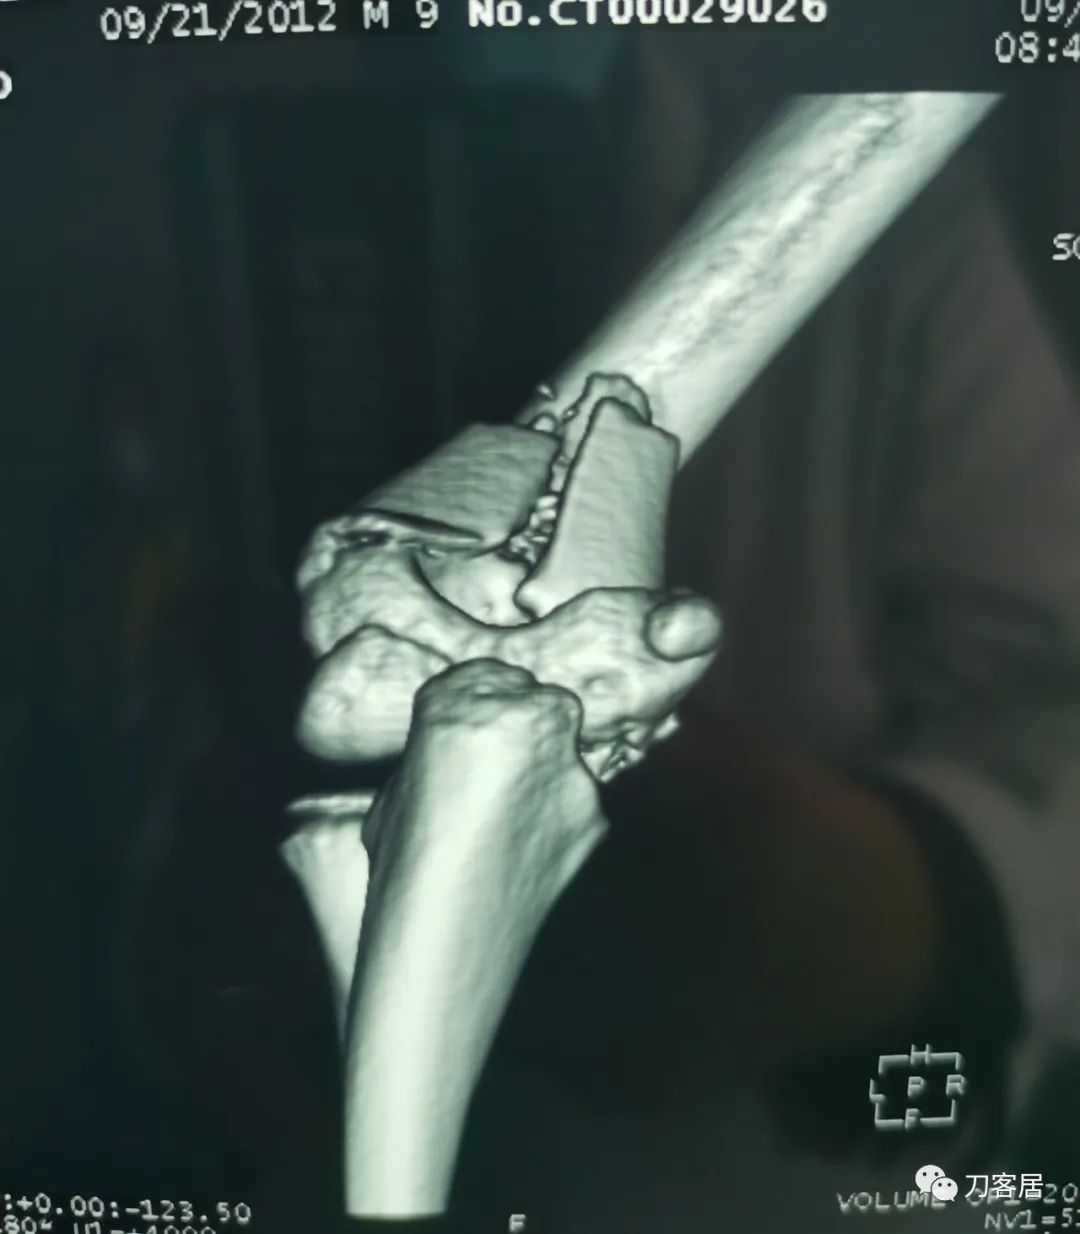

查体:左侧肘关节肿胀明显、疼痛、畸形,局部可见明显青紫瘀斑,左肘关节活动受限,肱骨远端环形压痛(+),局部可及异常活动及骨擦感形成,左上肢末梢桡动脉可触及,左侧腕关节及拇指背伸活动受限,左侧虎口区感觉麻木。辅助检查:自带X线及CT片示:左肱骨髁间粉碎性骨折。

入院诊断:1. 左肱骨髁间粉碎性骨折;2.左肱骨远端骨骺损伤;3. 左桡神经损伤。

20210922当地省中医院三维CT02